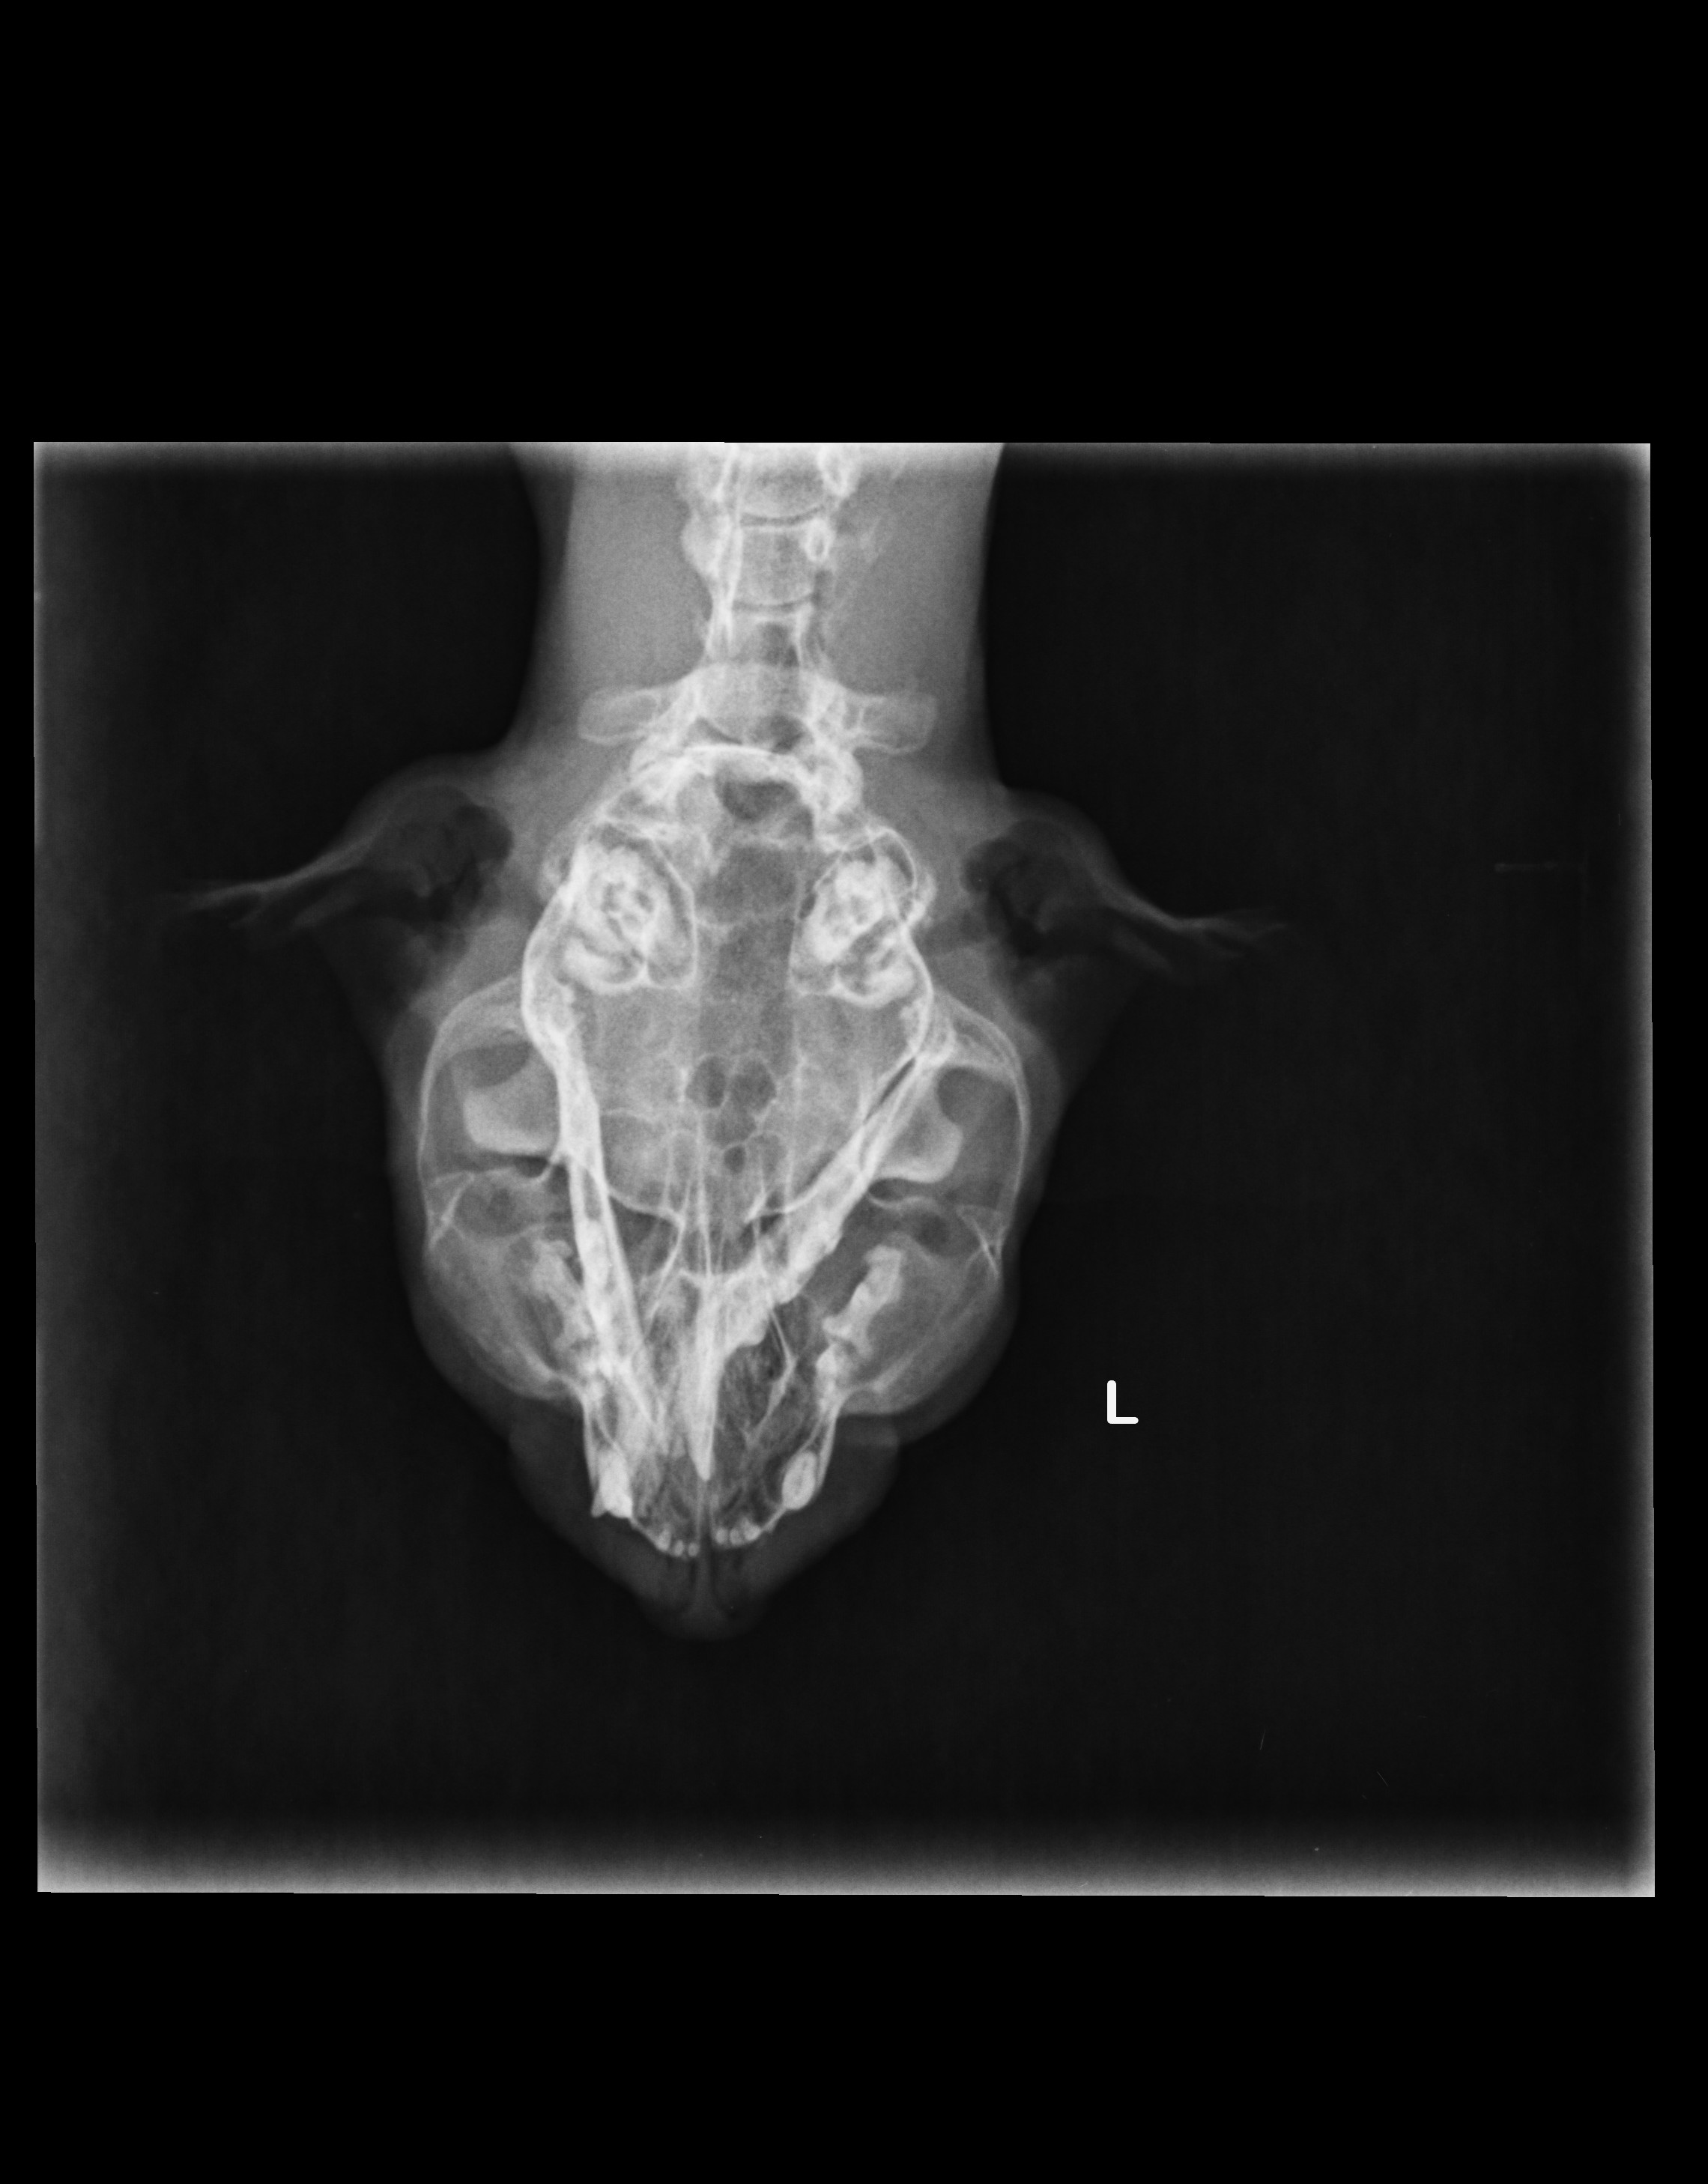

Craniu

Fractura mandibula